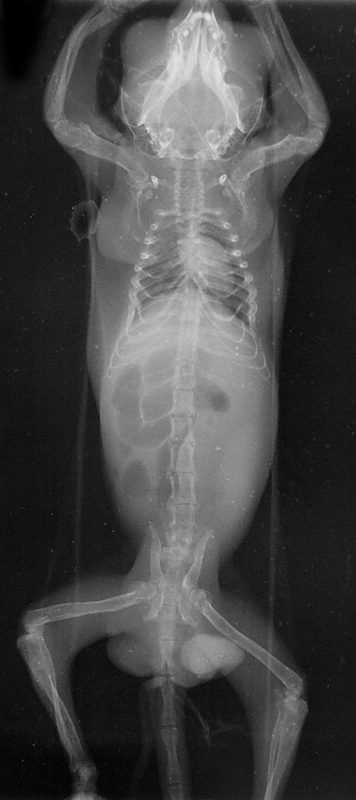

くる病のレントゲン写真

X線検査で骨の薄さと変形、骨折の有無などを確認します。

骨が薄くなったり、曲がると、フクロモモンガでは、特に四肢と骨盤に異常が認められます。

四肢が変形して、上手く歩けなくなり、這いつくばって歩くようになります。骨盤が変形すると、糞が出なくなり、便秘で苦しむようになります。これはある程度フクロモモンガが大きく成長してから見られることが多いです。カルシウム欠乏は、骨だけでなく、神経ならびに筋肉にも影響し、手足が震えたり、ピクピクと筋肉が動く症状がみられます。この状態になると死亡する可能性が高くなります。